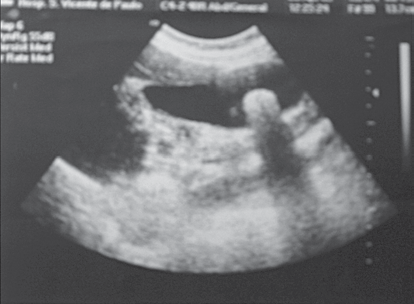

Observe a imagem.

Paciente masculino, 36 anos, apresenta o exame mostrado na imagem.

O tratamento cirúrgico está indicado pela maior possibilidade de

A imagem é compatível com